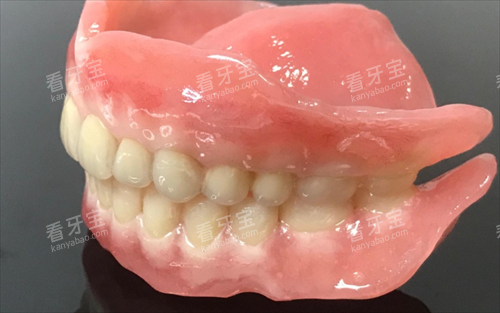

全口义齿

全口义齿需要完全贴合患者的口腔黏膜和颌骨形态,精度要求也很高。

智能化扫描能更准一些捕捉口腔的三维形态,制作出来的义齿贴合度更好,舒适度更高,建议优先选择。